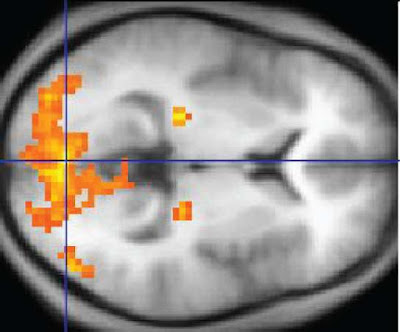

الانتباه له أبعاد عديدة، بما في ذلك القدرة على مواصلة الانتباه[5] أو استعادة التركيز عند تشتت الانتباه، والقدرة على تخزين المهام القادمة في الذاكرة العاملة. بالنسبة لهذه الدراسة الجديدة، قام تشون Chun وفريق بحث بقيادة كوانغسان راي يو Kwangsun Ray Yoo من جامعة ييل Yale باختزال البيانات[6] المأخوذة من مسوحات الدماغ للأشخاص أثناء قيامهم بسلسلة من المهام المتعلقة بالانتباه، مثل تمارين التركيز المستمر[5] ، ثم ربطوا تلك المعلومات بأنماط النشاط في مناطق الدماغ المختلفة. ثم قاموا بإنشاء نموذج حوسبي بحيث يكون حساسًا للغاية بحيث يمكنه التنبؤ بمدى أداء الفرد في مهمة متعلقة بالانتباه حتى عندما يكون الدماغ في حالة استراحة [في حالة لا يقوم الشخص بأي مهمة كما لو كان في حالة، ن، م، [7] .

قال تشون: ”خلايا الدماغ كلها مترابطة ببعضها [المترجم في الدماغ تريليون خلية عصبية وفيه ألف تريليون مشبك عصبي، بحسب[8] ، ويعمل بشكل دؤوب كما يعمل القلب النابض“. ”ما نتمكن من فعله هو أخذ كل أنماط نشاط الدماغ المركبة وتحليل البيانات لوضع بصمة لقدرة الدماغ على الانتباه.“

صورة الرنين المغناطيسي الوظيفي حيث مناطق الملونة بالأصفر تظهر نشاطًا متزايدًا.